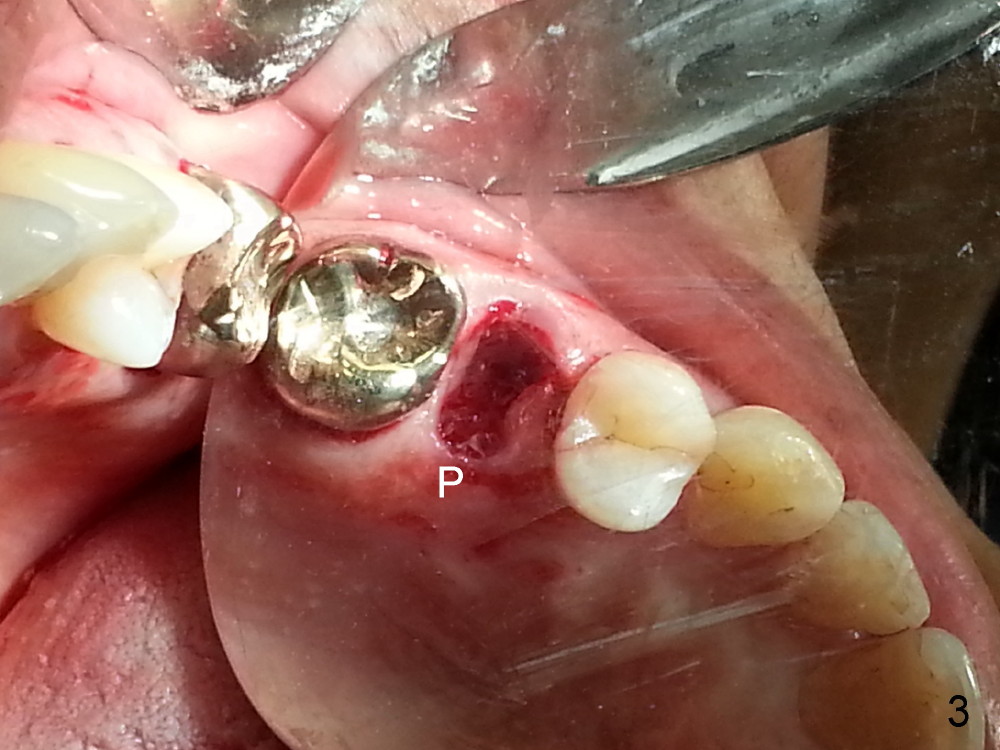

Grafting Following Immediate Implant (Photos Provided by Xue Steven, DDS)

The tooth #13 appears to be affected by periodontits and occlusal trauma (Fig.1*). After using a periotome (Fig.2), the tooth is extracted (Fig.3). The buccal flap is raised (Fig.4). Gingival graft is to be harvested from the site of #15 (Fig.5). The tissue is elevated buccally (Fig.6) and separated (Fig.7). The donor site is covered by a collagen membrane (Fig.8*). A diamond bur is used to induce bleeding from the socket (Fig.9*). Osteotomy is initiated (Fig.10) and enlarged (Fig.11,12). A tapered implant is being placed (Fig.13-15) following internal sinus lift (Fig.16,17). The implant is placed subcrestally, followed by bone graft (Fig.18), soft tissue graft (Fig.19), and suturing (Fig.20 <, Fig.21).